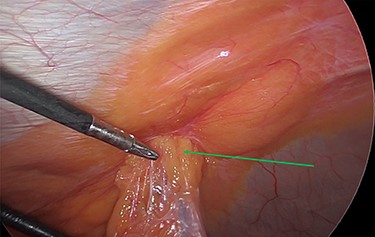

Intraoperatively, we noticed omentum incarcerated in the hernia sac (Fig. 2).

Laparoscopic view of the incarcerated omentum in the umbilical hernia (green arrow).